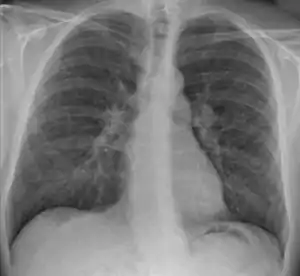

| پرتونگاری سینه که در آن التهاب غدد لنفاوی مخصوص به سارکوئیدوز در ناف ریه ها دیده میشود. | |

علائم این بیماری بسیار متغیر است. غالباً بهطور ناگهانی با احساس ضعف، تب، دردهای عضلانی و همچنین برآمدگی سرخ رنگ دردناک در ناحیه ساق پا شروع میشود. چشمها گاهی دردناک و گاهی بینایی ضعیف میگردد. غدههای لنفاوی ممکن است بزرگ شوند و آنها را به صورت تودههای دردناک در گردن، زیر بغل و کشاله ران با دست احساس کرد. بزرگی گرههای لنفاوی ناف ریه در قفسه سینه نیز شایع است. اگرچه هیچ گونه علائمی ندارد اما میتوان آنها را در رادیوگرافی تشخیص داد. ریه غالباً درگیر است و معمولاً علائمی ندارد. اگرچه ممکن است تنگی نفس و سرفه خشک پیدا شود. گاهی میزان کلسیم خون این افراد نیز افزایش مییابد.